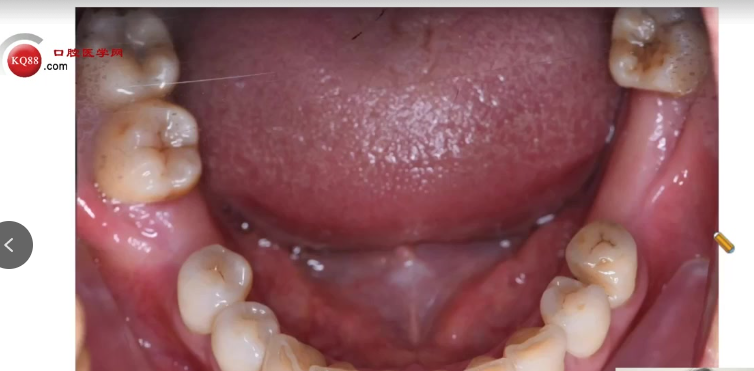

通俗解释:术前不仅要通过CBCT评估骨量、骨密度,还要了解患者缺失牙的原因(如牙周病、外伤等),并确保邻牙及软组织健康。

术前准备:CBCT评估骨量,选择合适种植体系统(如诺贝尔、奥齿泰等)。

手术操作:麻醉后切开、翻瓣,逐级扩孔(注意提拉与冷却),植入种植体。